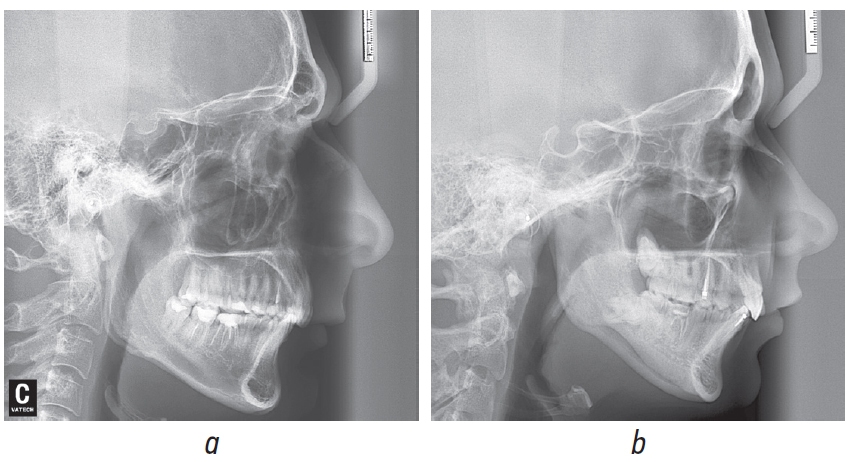

Рентгеноцефалометрический анализ боковых телерентгенограмм (ТРГ) (рис. 5 а, b) выявил у обоих пациентов верхнюю и нижнюю ретро- и микрогнатию, ретрузию верхних резцов, увеличение выпуклости лицевого профиля, лица, заднее положение подбородочного отдела. Анализ ТРГ в прямой проекции, выполненной пациентке Ж. по показаниям, — асимметрию нижней челюсти, выражающуюся в смещении подбородочного отдела влево и разнице в длине ее ветвей.

Рис. 5. Боковые телерентгенограммы пациента Ч. (а) и пациентки Ж. (b) до лечения

Fig. 5. Lateral teleradiography of patient Ch. (a) and patient Zh. (b) before treatment